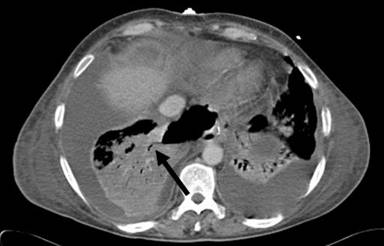

A 40-year-old woman had been admitted for an endoscopic drainage of pseudocyst that developed secondary to gallstone-induced pancreatitis treated elsewhere. The procedure needed to be postponed due to development of a large pulmonary embolus for which the patient was anti-coagulated. As the pseudocyst decreased in size (5 cm diameter) on CT imaging, no drainage was attempted on that admission. Four months later she was re-admitted as an emergency with acute upper abdominal pain and vomiting. On arrival, the patient was unwell, dehydrated and tachycardic. The clinical diagnosis of pancreatitis was confirmed by the raised serum amylase of 203 U/L (reference range: 0-135 U/L). The APACHE II score was 11 (adjusted predicted death rate of 19.6%). Within 12 hours she rapidly deteriorated, developed type I respiratory failure and required respiratory support. The contrast CT revealed that the known pseudocyst had increased in size, measuring 11.7x5.0 cm with features of pancreatic necrosis (Figure 1) and large bilateral pleural effusions. It extended into the posterior mediastineum around the oesophagus. Bilateral chest drains were inserted and ionotropic cardiac support implemented. At this stage her APACHE II score was calculated at 20 (adjusted predicted death rate of 47.6%). Since the patient continued to deteriorate, endotracheal ventilation became necessary. Immediately after insertion of the endotracheal tube, 2 L of amylase rich fluid (26,562 U/L) spontaneously drained via the tube. The diagnosis of a pancreaticobronchial fistula was confirmed on the repeated contrast CT (7 days after the admission), which showed a large amount of gas inside the cyst and evidence of fistulation into the right lower lobe bronchi (Figures 2 and 3). The pseudocyst was drained percutaneously under the CT guidance via the transgastric route and the pleural collections by bilateral chest tubes (amylase: 13,995 U/L). Subsequent tubogram and bronchoscopy did not confirm the fistulous connection with the bronchial tree. Subsequently, 16 days following the admission, due to progressive deterioration, the patient underwent an open pancreatic necrosectomy. Intraoperatively, the pancreatic collection was tracking cranially towards the diaphragm. With every lung inflation by the ventilator air was seen to escape from the peripancreatic collection indicating a communication with the airway. Therefore, following debridement of the peripancreatic tissues, an underwater-seal drain was inserted into the cavity. Four days after the necrosectomy the woman was weaned off the ventilator and the air leak in the under water seal drain ceased within the next 5 days. The abdominal drains were removed on the 11th postoperative day. The patient returned to the surgical ward after 4 weeks of intensive therapy unit (APACHE II score 1, adjusted predicted death rate 5.4%) and following a prolonged period of convalescence, was discharged home 2 months later. The open drainage of the cyst and the pleural collections combined with supportive measures such as intravenous octreotide infusion and parental nutrition (L-alanyl-L-glutamine-supplemented parental nutrition) for 24 days resulted in the successful recovery.

Figure 2. CT 7 days post admission demonstrating bronchial fistula communicating with pancreatic pseudocyst (see arrow). |